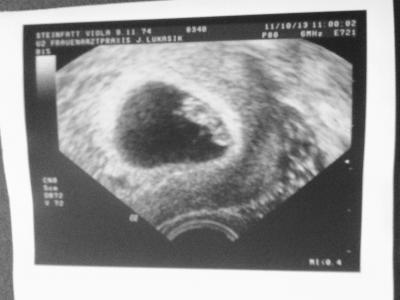

Hallo,mein Name ist Viola und ich würde gern bei Euch einsteigen.Ich wünsche uns allen eine Gute Fahrt bis in den Mai.Das Bilchen ist vom 11.10.2013 (8 SSW)

Bild zu Ist noch ein Plätzchen frei ? - Forum für Mai - Mamis